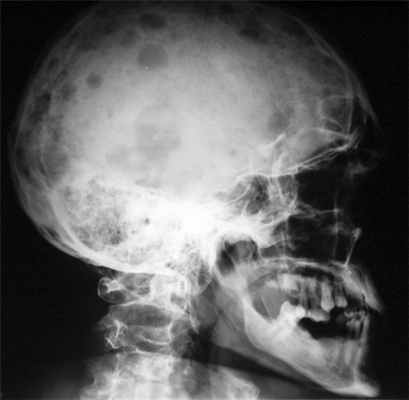

- рентгенография таза, черепа, грудной клетки;